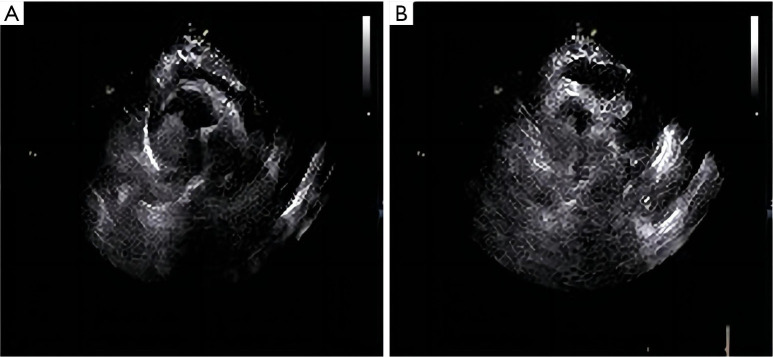

Case description: The patient was diagnosed with renal cell carcinoma and underwent surgical radical resection, no special treatment was performed after surgery. Metastases of the right thigh muscles and both lungs were found after 4 years, and the patient was treated with 1 cycle of sunitinib + sintilimab. The patient had sudden symptoms of circulatory obstruction, computed tomography angiography (CTA) showed that the right atrial mass was occupied, and cardiac surgery was performed, and the postoperative pathology confirmed that it was kidney cancer heart metastasis, the operation was successful. The patient had aggravated lung infection after 2 weeks of follow-up, and the symptoms improved after treatment with antibiotics, anticoagulation, and nutritional support. This operation relieved the patient's circulatory embolism, saved the patient's life, and prolonged the patient's survival.